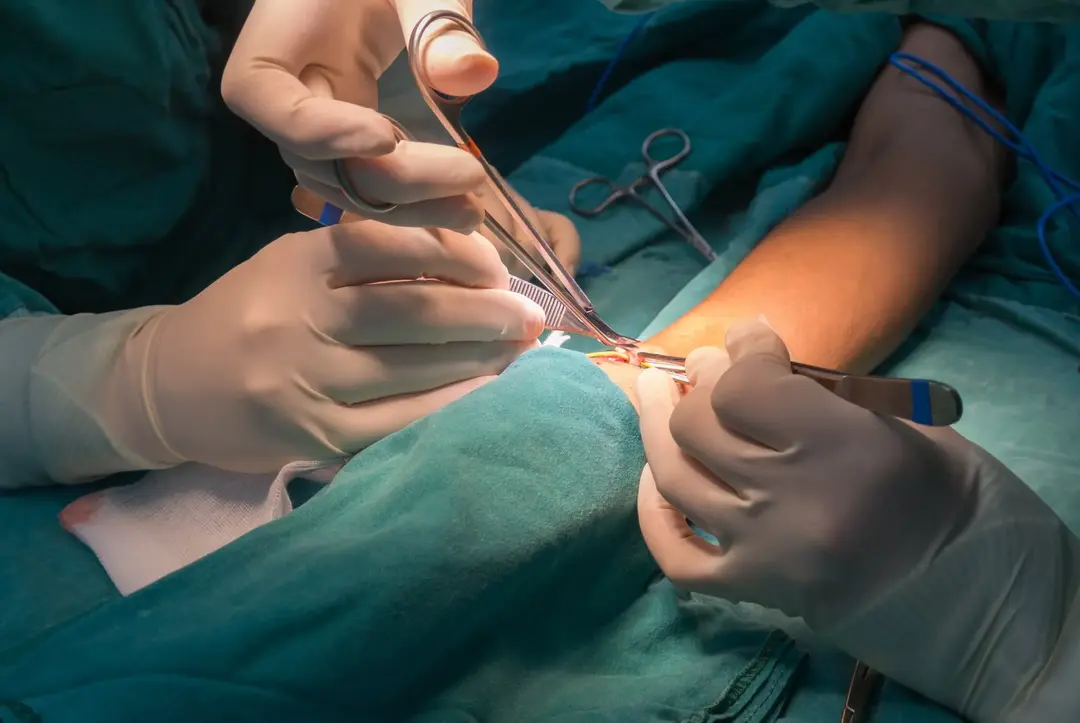

Paciente em Diálise Engravidou: Como Conduzir com Segurança?

Paciente em Diálise Engravidou: Como Conduzir com Segurança?

Gestação é hemodiálise é uma situação de muito risco, o nefrologista pode fazer muita diferença no desfecho materno-fetal, confere essas dicas de pontos que devemos estar atentos na prescrição de diálise de uma paciente gestante!